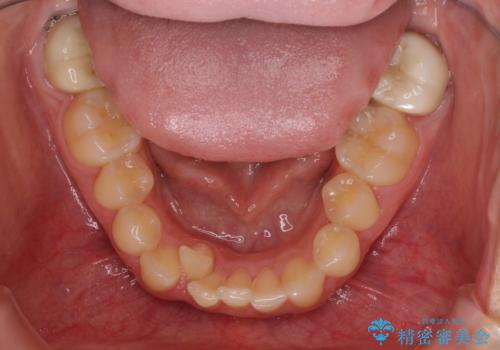

- 上顎の重なっている前歯を気にして来院された患者様です。

八重歯改善には抜歯が必要で、八重歯の移動量が多く、更には右側にずれている正中を改善する必要がありました。

インビザライン単体での治療は困難と判断し、補助装置により八重歯移動後にインビザラインを用いることとしました。

インビザラインでは治療期間が延びることが予想されたため、ワイヤー矯正を提案しましたが、セラミッククラウンが多く、壊すあるいは傷が付く可能性があることから、長期間であってもインビザラインを選択されました。